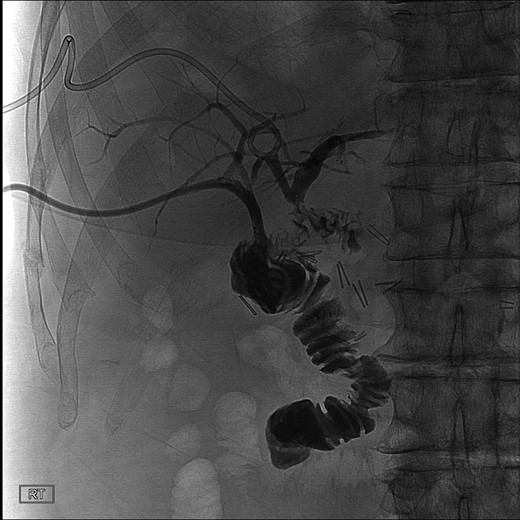

The patient was placed on broad spectrum antibiotics and treated for atrial fibrillation with rapid ventricular response. Laboratory workup revealed a bilirubin level of 17 mg/dl, as well as profound protein–calorie malnutrition with an albumin of 1.9 gm/dl. A percutaneous cholangiogram was performed confirming a hilar ligation of his hepatic duct with inability to pass a wire or catheter distally. A right posterior and right anterior percutaneous cholangiogram catheter was placed for definitive biliary diversion (Fig. 2). The patient was then managed with high calorie, high protein enteral nutrition through a nasogastric Dobhoff tube for approximately 7 days until able to tolerate appropriate oral intake for discharge. He was scheduled for follow-up in 2 weeks.

Cholangiogram of right intrahepatic ducts with abrupt cutoff at surgical clips.